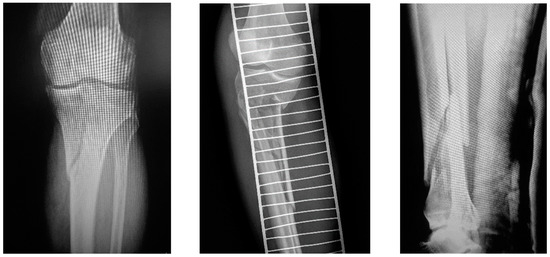

Single-Stage Externalized Locked Plating for Treatment of Unstable Meta-Diaphyseal Tibial Fractures

by Biser Makelov, Dominic Mischler, Peter Varga, Theerachai Apivatthakakul, James W. A. Fletcher, Deyan Veselinov, Till Berk, Dimitur Raykov and Boyko Gueorguiev

J. Clin. Med. 2023, 12(4), 1600; https://doi.org/10.3390/jcm12041600 - 17 Feb 2023

Cited by 3 | Viewed by 4965

(1) Background: Unstable meta-diaphyseal tibial fractures represent a heterogeneous group of injuries. Recently, good clinical results have been reported when applying a technique of externalized locked plating in appropriate cases, highlighting its advantage in terms of less additional tissue injury compared with conventional [...] Read more.

(1) Background: Unstable meta-diaphyseal tibial fractures represent a heterogeneous group of injuries. Recently, good clinical results have been reported when applying a technique of externalized locked plating in appropriate cases, highlighting its advantage in terms of less additional tissue injury compared with conventional methods of fracture fixation. The aims of this prospective clinical cohort study were, firstly, to investigate the biomechanical and clinical feasibility and, secondly, to evaluate the clinical and functional outcomes of single-stage externalized locked plating for treatment of unstable, proximal (intra- and extra-articular) and distal (extra-articular), meta-diaphyseal tibial fractures. (2) Methods: Patients, who matched the inclusion criteria of sustaining a high-energy unstable meta-diaphyseal tibial fracture, were identified prospectively for single-stage externalized locked plating at a single trauma hospital in the period from April 2013 to December 2022. (3) Results: Eighteen patients were included in the study. Average follow-up was 21.4 ± 12.3 months, with 94% of the fractures healing without complications. The healing time was 21.1 ± 4.6 weeks, being significantly shorter for patients with proximal extra- versus intra-articular meta-diaphyseal tibial fractures, p = 0.04. Good and excellent functional outcomes in terms of HSS and AOFAS scores, and knee and ankle joints range of motion were observed among all patients, with no registered implant breakage, deep infection, and non-union. (4) Conclusions: Single-stage externalized locked plating of unstable meta-diaphyseal tibial fractures provides adequate stability of fixation with promising clinical results and represents an attractive alternative to the conventional methods of external fixation when inclusion criteria and rehabilitation protocol are strictly followed. Further experimental studies and randomized multicentric clinical trials with larger series of patients are necessary to pave the way of its use in clinical practice. Full article

(This article belongs to the Section Orthopedics)

Show Figures

Figure 1